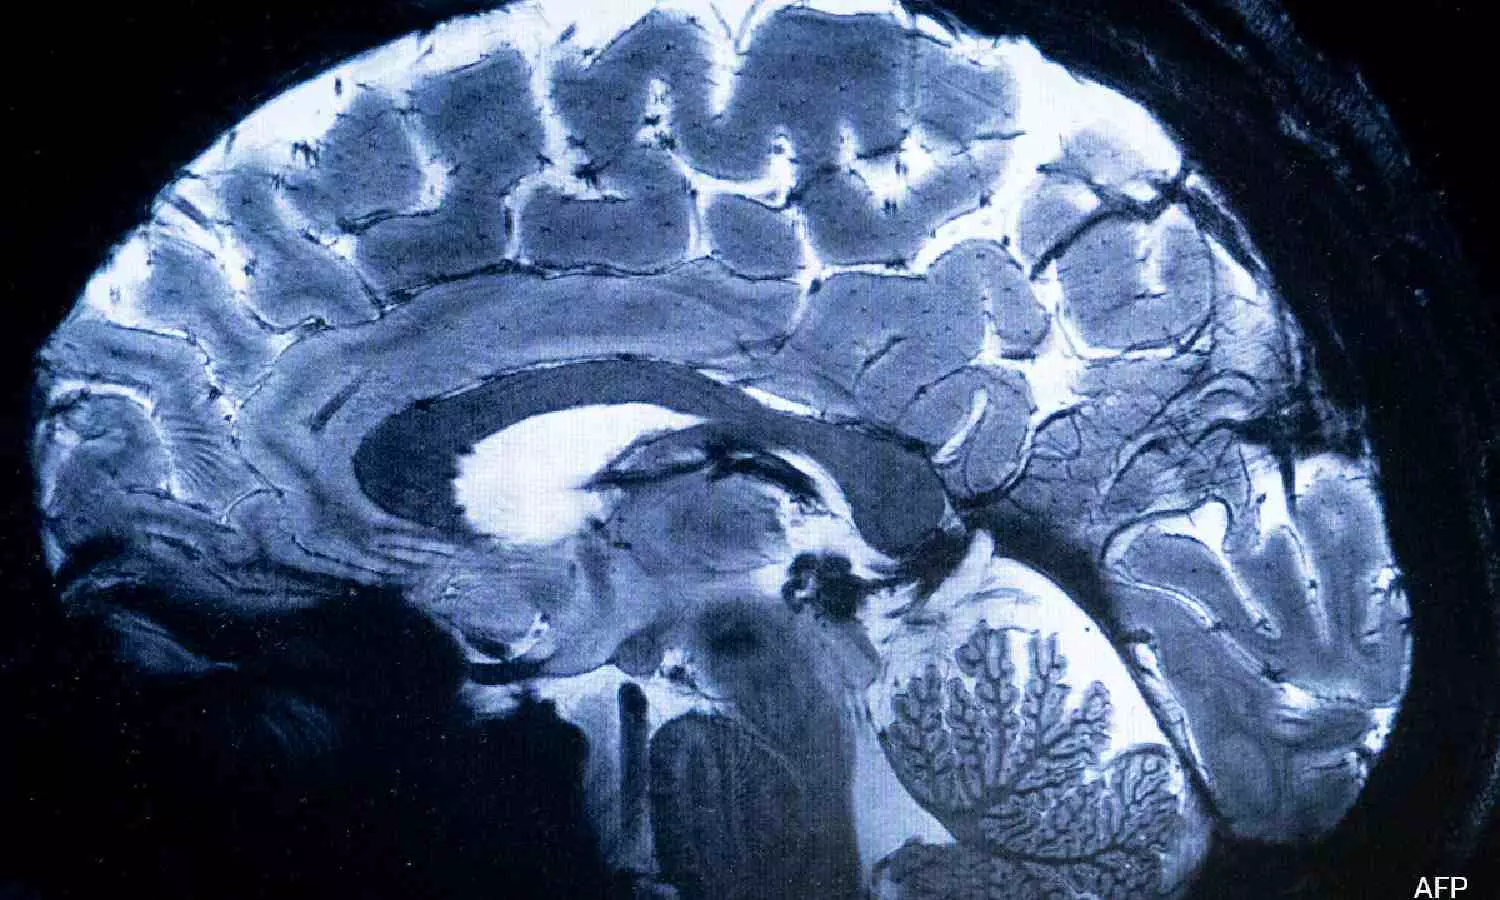

SACLAY [France]: The world's most powerful MRI scanner has delivered its first images of human brains, reaching a new level of precision that is hoped will shed more light on our mysterious minds -- and the illnesses that haunt them.

This power allows the machine to scan images with 10 times more precision than the MRIs commonly used in hospitals, whose power does not normally exceed three teslas.

On a computer screen, Vignaud compared images taken by this mighty scanner, dubbed Iseult, with those from a normal MRI.

"With this machine, we can see the tiny vessels which feed the cerebral cortex, or details of the cerebellum which were almost invisible until now," he said.